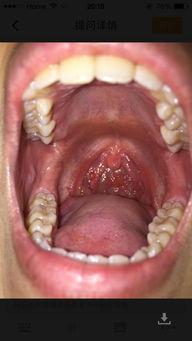

3. 口腔问题:吃白瓜时,如果口腔内有溃疡、炎症等问题,可能会刺激喉咙,导致喉咙痛。这可真是让人心疼啊!